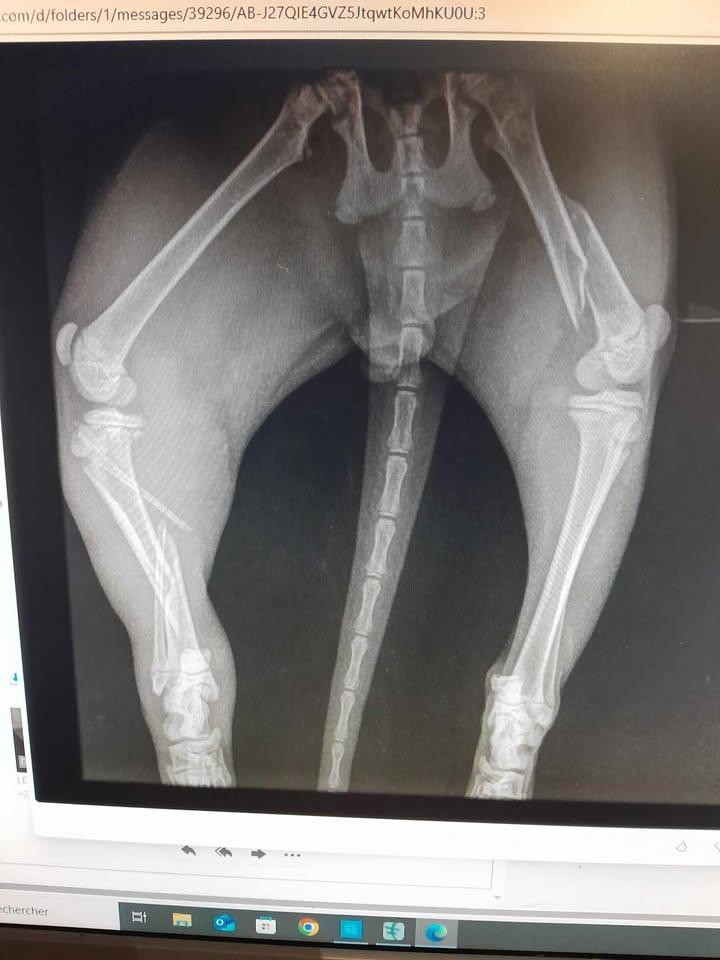

Apache est avec nous depuis un petit moment puisqu'il avait environ 2 mois et demi à son arrivé. Il était en piteux état. Tibia gauche cassé, fémur gauche cassé et tête du fémur droite cassée. Malgré le cout exorbitant (1300 euros pour la pose des broches et 800 pour les retirer à la consolidation) nous l'avons fait opéré.